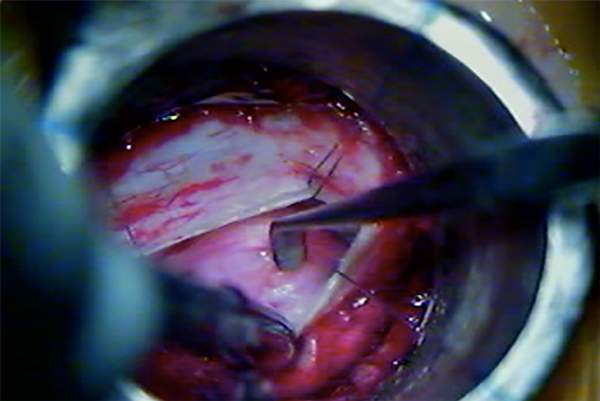

Cuando ya se encuentran en tracción los 4 puntos de reparo dural, los extremos de la incisión se aproximan entre sí, y eso permite incidir con bisturí dichos extremos para realizar una nueva tracción de los puntos de reparo, y así, una mayor exposición lateral (Fig. 7, 8 y 9).

Fig. 7: Ojal dural mediante retracción dural transtubular

Fig. 8: Disección tumoral separando la duramadre por apertura insuficiente.

Fig. 9: Exposición del contenido intradural mediante retracción dural percutánea.

DISCUSION